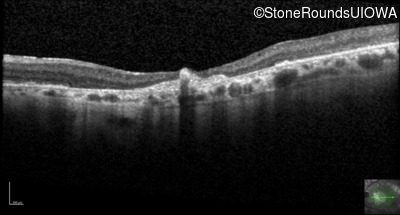

Optical Coherence Tomography - Right - 20/80

Exemplar / OCT Stack

OCT Stack